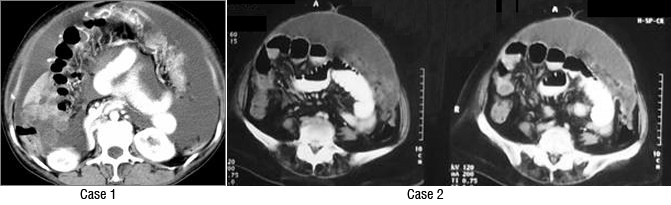

Stage 3: peritoneal implants outside pelvis or inguinal or retroperitoneal lymphadenopathy. Implants can be omentum, liver, parietal peritoneum. Peritoneal dissemination is characterised by peritoneal thickening, nodular lesion, stellate nodules located within mesentery or omentum. Stage 3a, b, c differ in size of lesion- 3a-tumour grossly limited to pelvis and gross ascites; 3b-peritoneal implant 2cms or less; 3c-implant size is more than 2cms . Retroperitoneal and inguinal adenopathy qualifies as stage 3c (Figures 6, 7 & 8).

Figure 8: Two different cases of carcinoma of ovary with omental and peritoneal thickening stage 3.